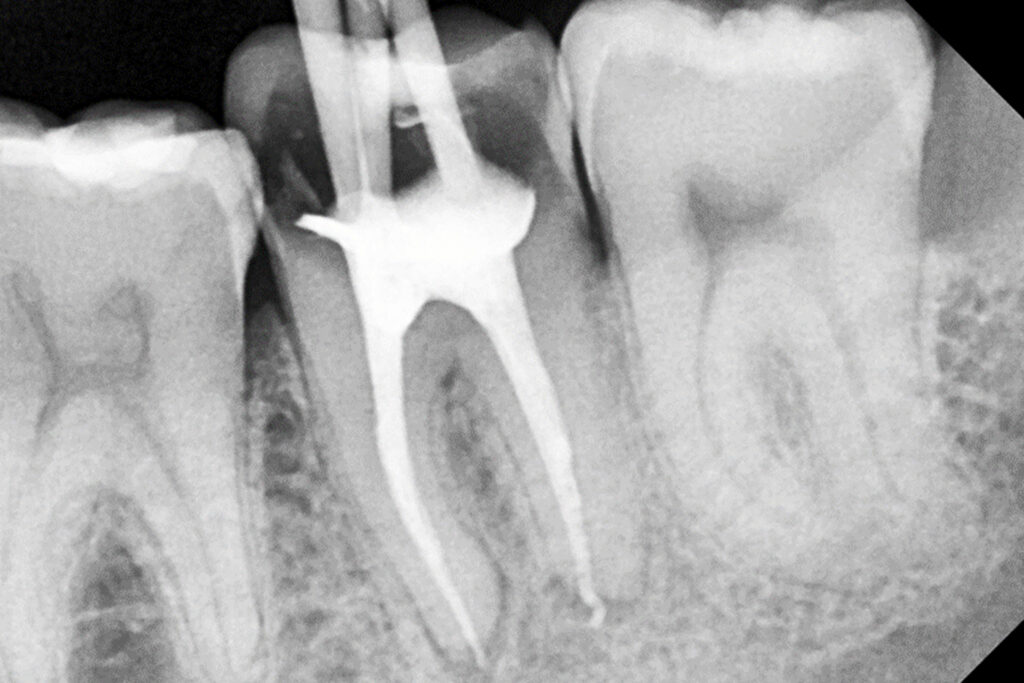

L’Endodòncia és el tractament dels conductes radiculars que cal realitzar quan la polpa dental (nervi) s’ha vist afectat (per càries profundes, traumatismes, fractures o quists, entre altres). Es tracta de localitzar, netejar i sellar els conductes radiculars, per posteriorment restaurar el teixit dental destruït i així poder conservar la dent i evitar-ne l’extracció.

A la nostra clínica apliquem tècniques d’endodòncia rotatòria, amb localitzadors d’àpex, radiografies digitals i materials d’última generació per tal de poder proporcionar un resultat efectiu dels nostres tractaments a llarg termini.